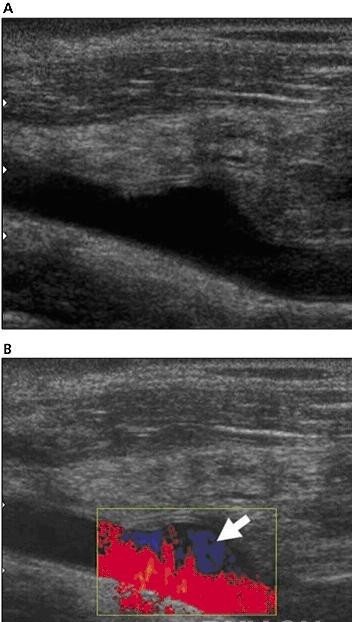

six months after the transplantation, a neck ultrasonographic scan was performed with a high-resolution linear transducer (voluson 730 pro; ge healthcare, waukesha, wi) that showed the transplanted thyroid gland anterior and caudal to the native thyroid (figure 1, a and b). both glands were normal in echogenicity and size. gray scale real-time ultrasonography showed a normal appearance of the inferior transplanted thyroid arteries. color doppler ultrasonography proved vascular perfusion and allowed visualization of the right superior thyroid artery. power doppler ultrasonography showed normal flow within the transplanted thyroid gland (figure 1c). b-mode ultrasonography showed normal dilatation of the carotid artery at the site of the arterial anastomosis (figure 2a); color doppler ultrasonography showed reversal of flow at that point (figure 2b). spectral doppler ultrasonography was performed at the origin of transplanted thyroid arteries and showed peak systolic speeds between 32 and 48 cm/s and end-diastolic velocities between 9 and 13 cm/s with high-resistance waveforms (figure 3b). the evaluation of venous anastomoses was not possible because there were no changes in internal jugular veins allowing differentiation from native thyroid veins. spectral analysis showed both arterial and venous flow within the transplanted thyroid gland, the latter being an indirect sign of patency of the venous anastomoses.

移植手术中将供者气管近端与第一个气管环吻合,将远端在隆凸水平上3cm处吻合。根据手术医生从先前的动物试验模型中发展来的技术,将气管连带甲状腺进行了移植。同时将供者甲状腺下动脉和受者的颈总动脉吻合,将右甲状腺上动脉和受者同侧颈外动脉吻合,甲状腺中静脉与颈内静脉吻合,甲状腺下静脉与无名静脉吻合。2个月后,dsa显示血管(动脉)灌注良好,检查期间静脉相显示不清。病人术后进展平稳,除了有过一次的乳糜胸但也解决了。术后病人拔除了插管,也没出现呼吸困难,予以免疫抑制剂治疗防止排异反应。移植手术后6个月,应用高分辨率的探头行颈部超声检查(ge voluson730 pro),显示移植的甲状腺位于前面,自身甲状腺在后(图1,a和b),两腺体的回声和大小正常。灰阶实时超声扫描显示移植甲状腺下动脉形状正常。彩色多普勒超声证实血管充盈良好,右侧甲状腺上动脉充盈良好。能量多普勒显示移植甲状腺内血流正常(图1,c)。b型超声显示动脉吻合处颈动脉正常扩张(图2,a)。彩色多普勒显示此处血流反转(图2,b)。频谱多普勒超声显示移植甲状腺动脉起始点的收缩期峰值流速在32-48cm/s,舒张末期流速在9-13cm/s,呈高阻力波形(图3,b)。由于无法区分自身甲状腺静脉和颈内静脉,因此静脉吻合处的检查不能评估。频谱多普勒显示移植甲状腺内的动脉和静脉分布正常。后者间接表明了静脉吻合处是开放的。

图3 a,彩色多普勒图像显示18岁患者气管移植后的移植甲状腺左上动脉呈环状(黑箭头),起源于左侧颈总动脉(白箭头)。b,频谱多普勒图像显示移植甲状腺动脉起源处的高阻力频谱。